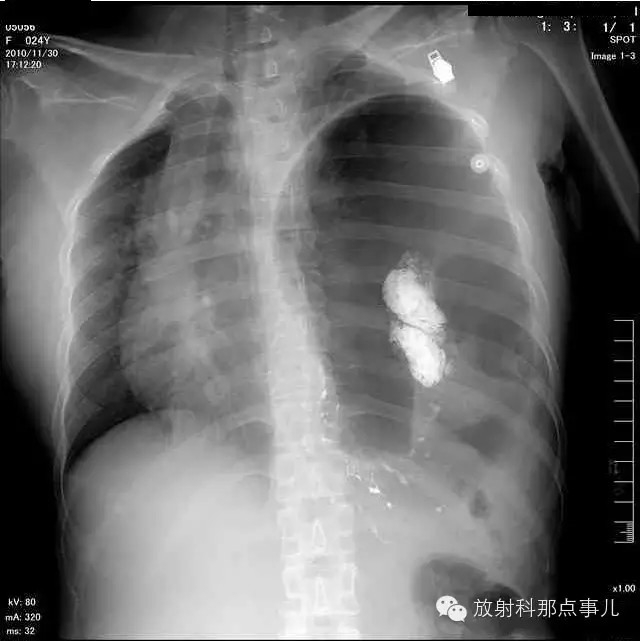

大部分胃、脾及横结肠均经过胸肋三角疝入左侧胸腔内,并见疝环形成。

考虑该患者因生产过程中腹压急剧升高,导致腹内脏器经膈肌缺损或薄弱部位进入胸腔内。